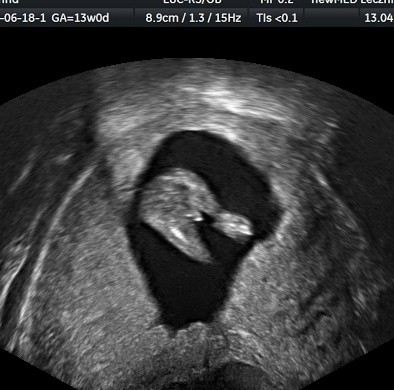

A tak w ogóle to u mnie zgodnie z moim przewidywaniem (seks w owulację) ma być kolejny chłopak. Trochę szkoda bo marzyłam o siostrze dla córci, no ale wychowamy jak swoje ;) I takie zdjęcie rzekomego siusiaka dostałam:

Zobacz załącznik 846583